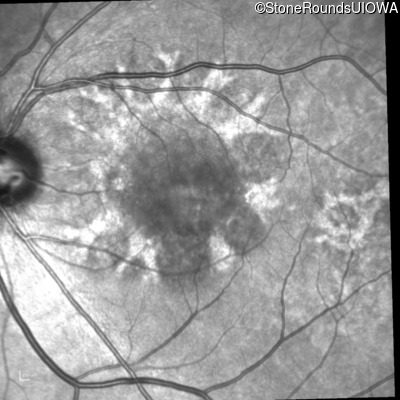

Blue Autofluorescence - Right - 20/25

Exemplar